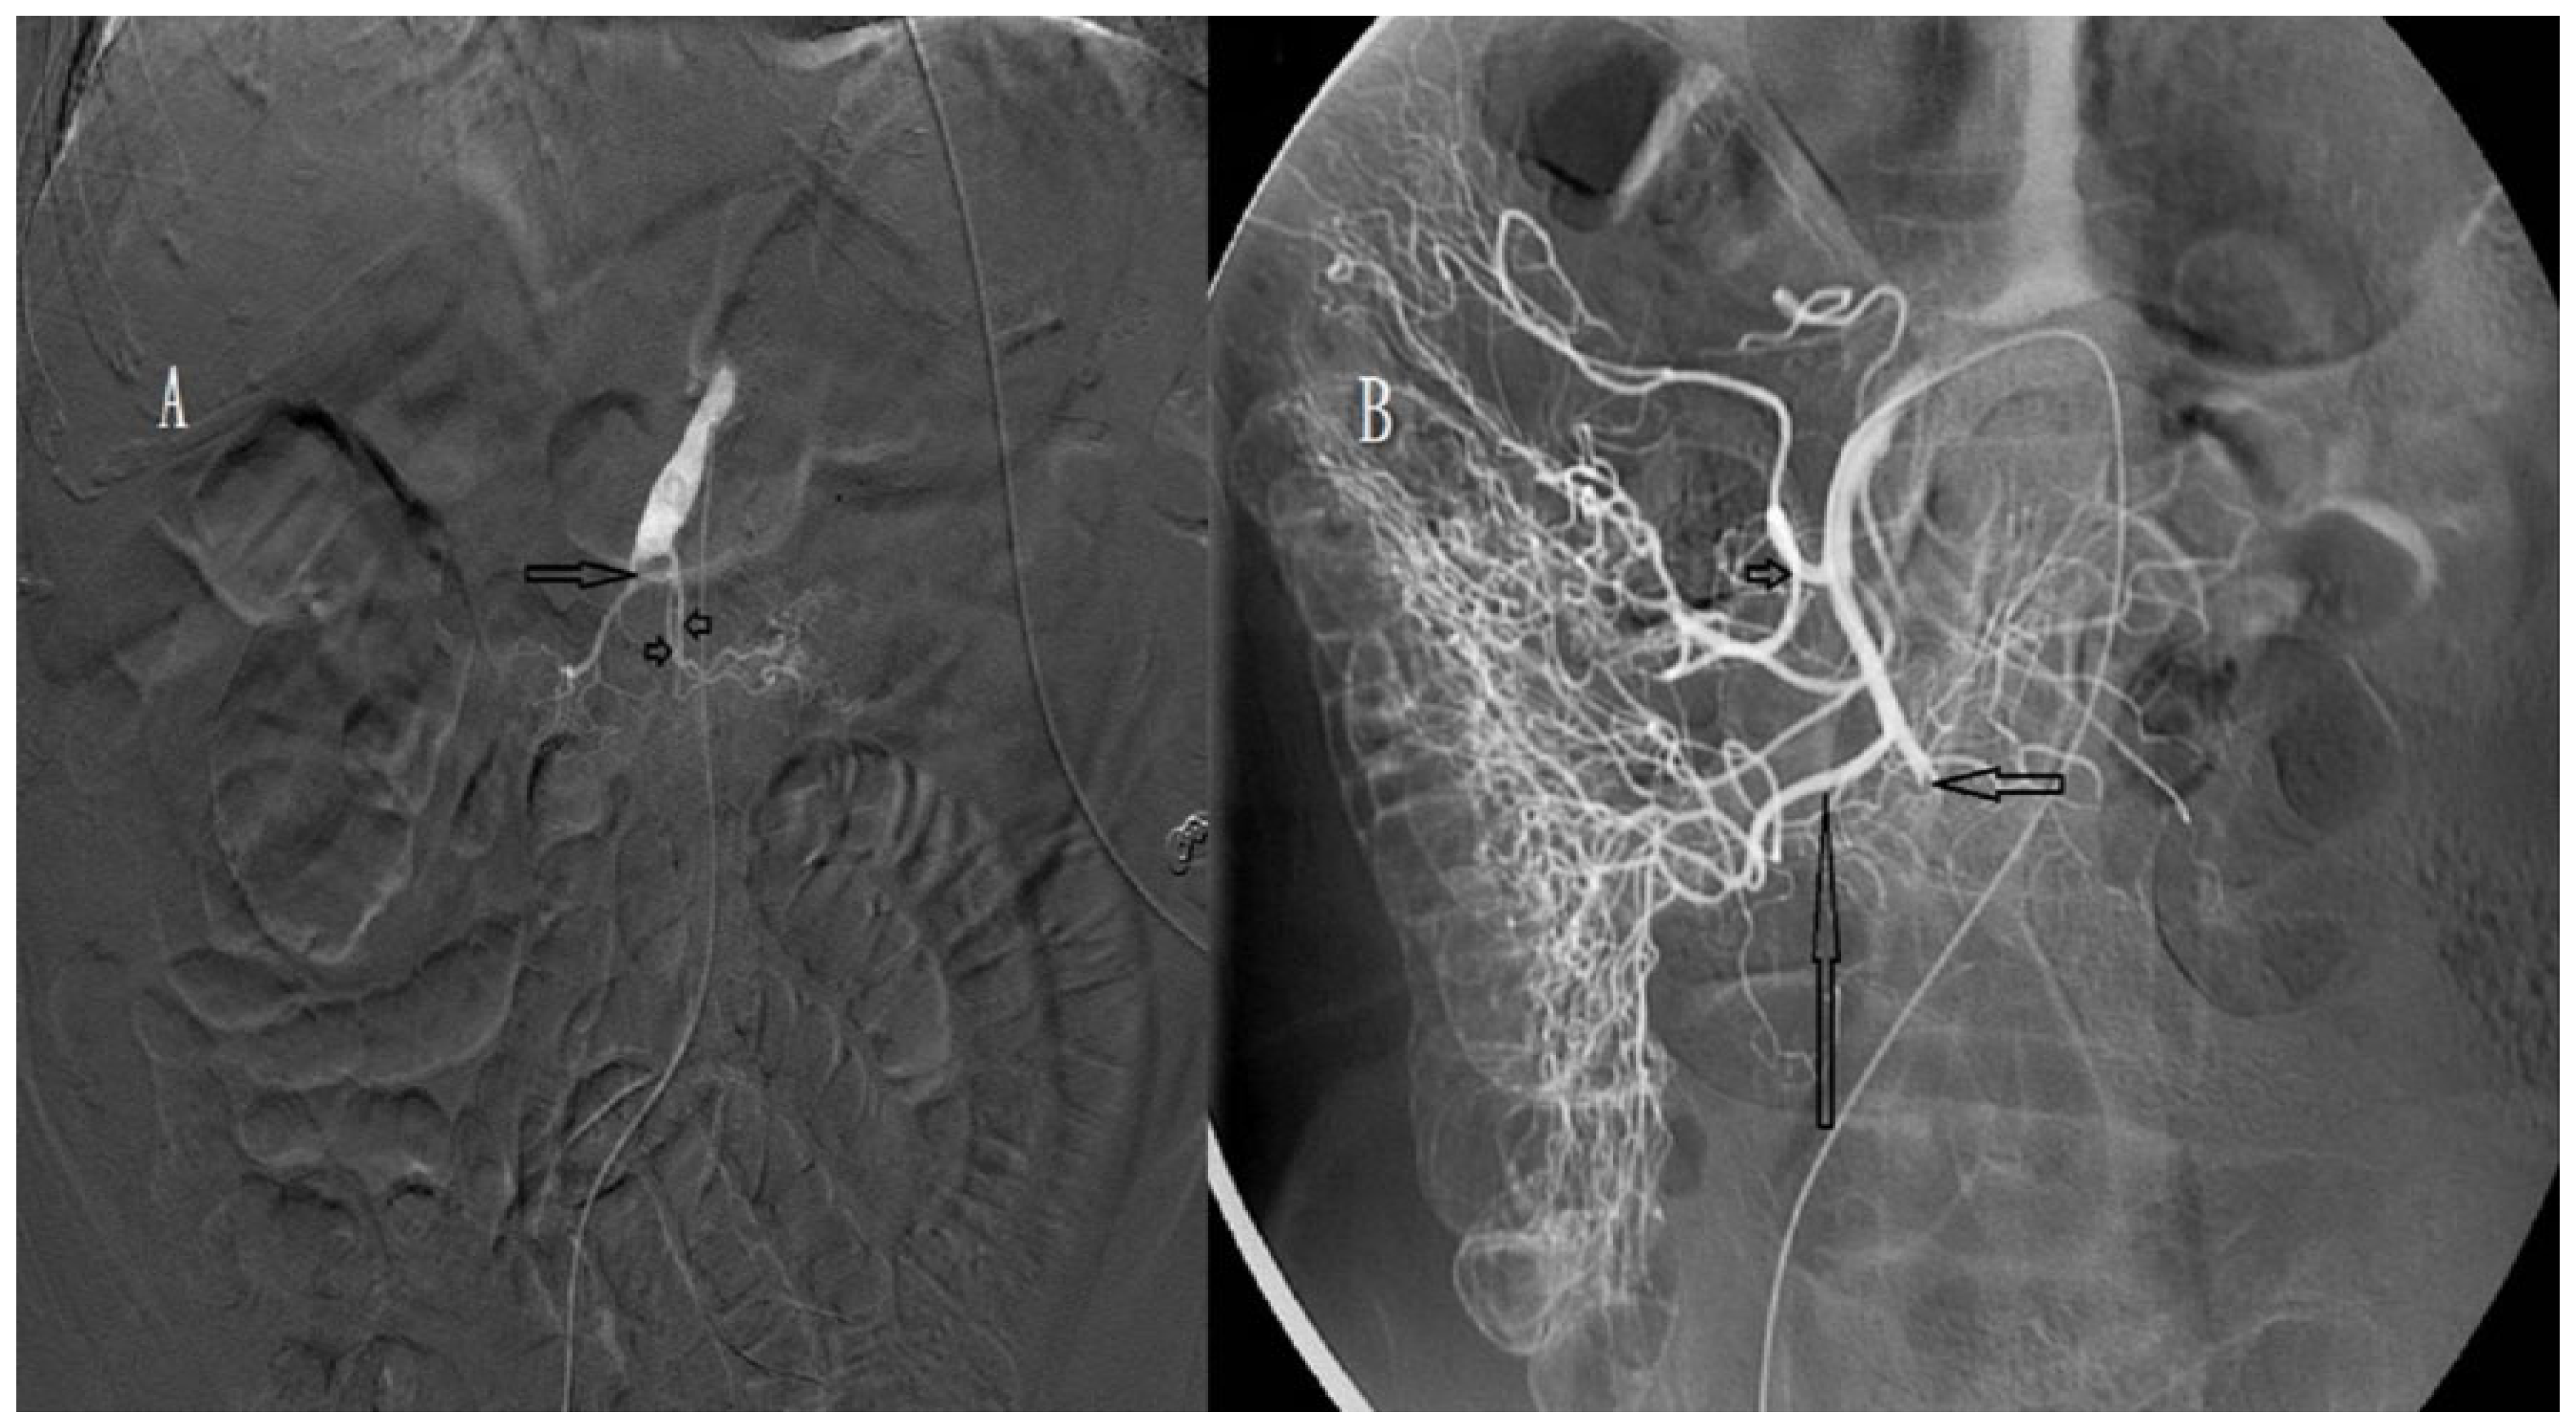

2.4. Procedure